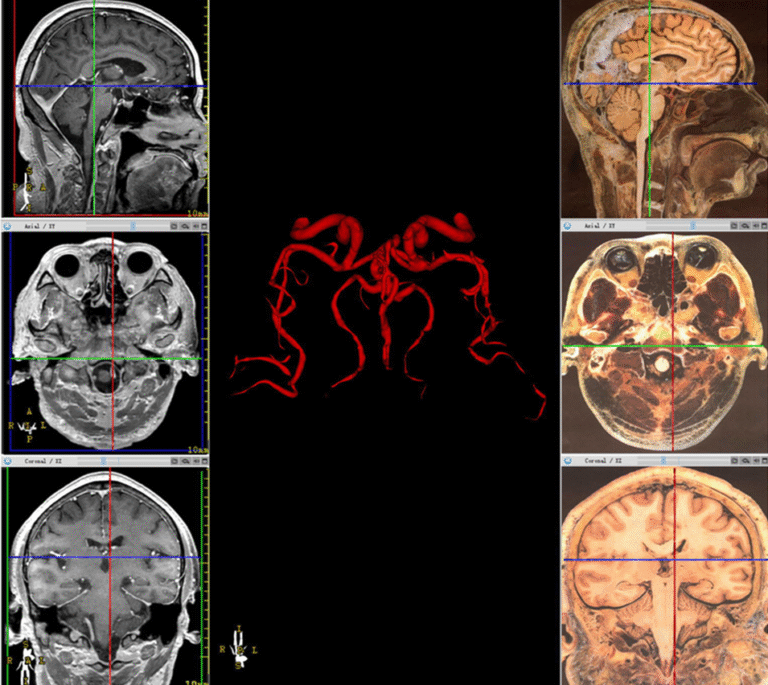

In the ever-evolving field of healthcare technology, anatomical 3D models are revolutionizing diagnostics, surgical planning, and patient education. By converting traditional medical scans into detailed 3D visualizations, clinicians can now interact with organs and tissues in ways that were once unimaginable.

In this guide, we’ll walk you through how medical image segmentation and 3D medical imaging techniques are used to transform 2D medical scans into lifelike, medical 3D models.

Once segmentation is complete, the software converts the isolated 2D slices into a 3D model by stacking and rendering them in a volumetric format.

At this stage, the medical 3D modeling process generates a mesh that outlines the surface of the anatomical structure.